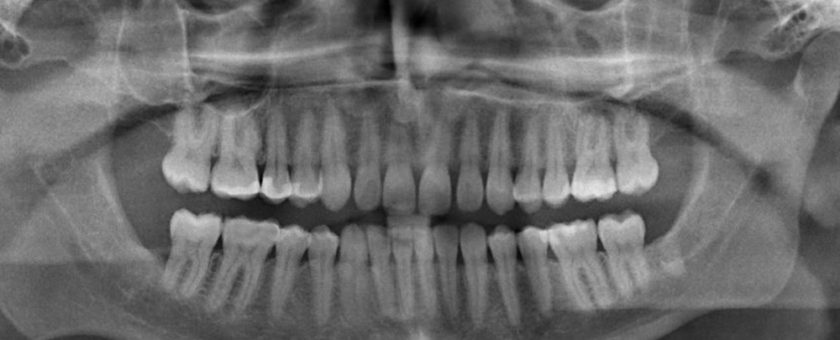

Il dentista dopo aver visionato la radiografia, ha controllato la mobilità dei denti con la mani senza usare gli strumenti idonei.